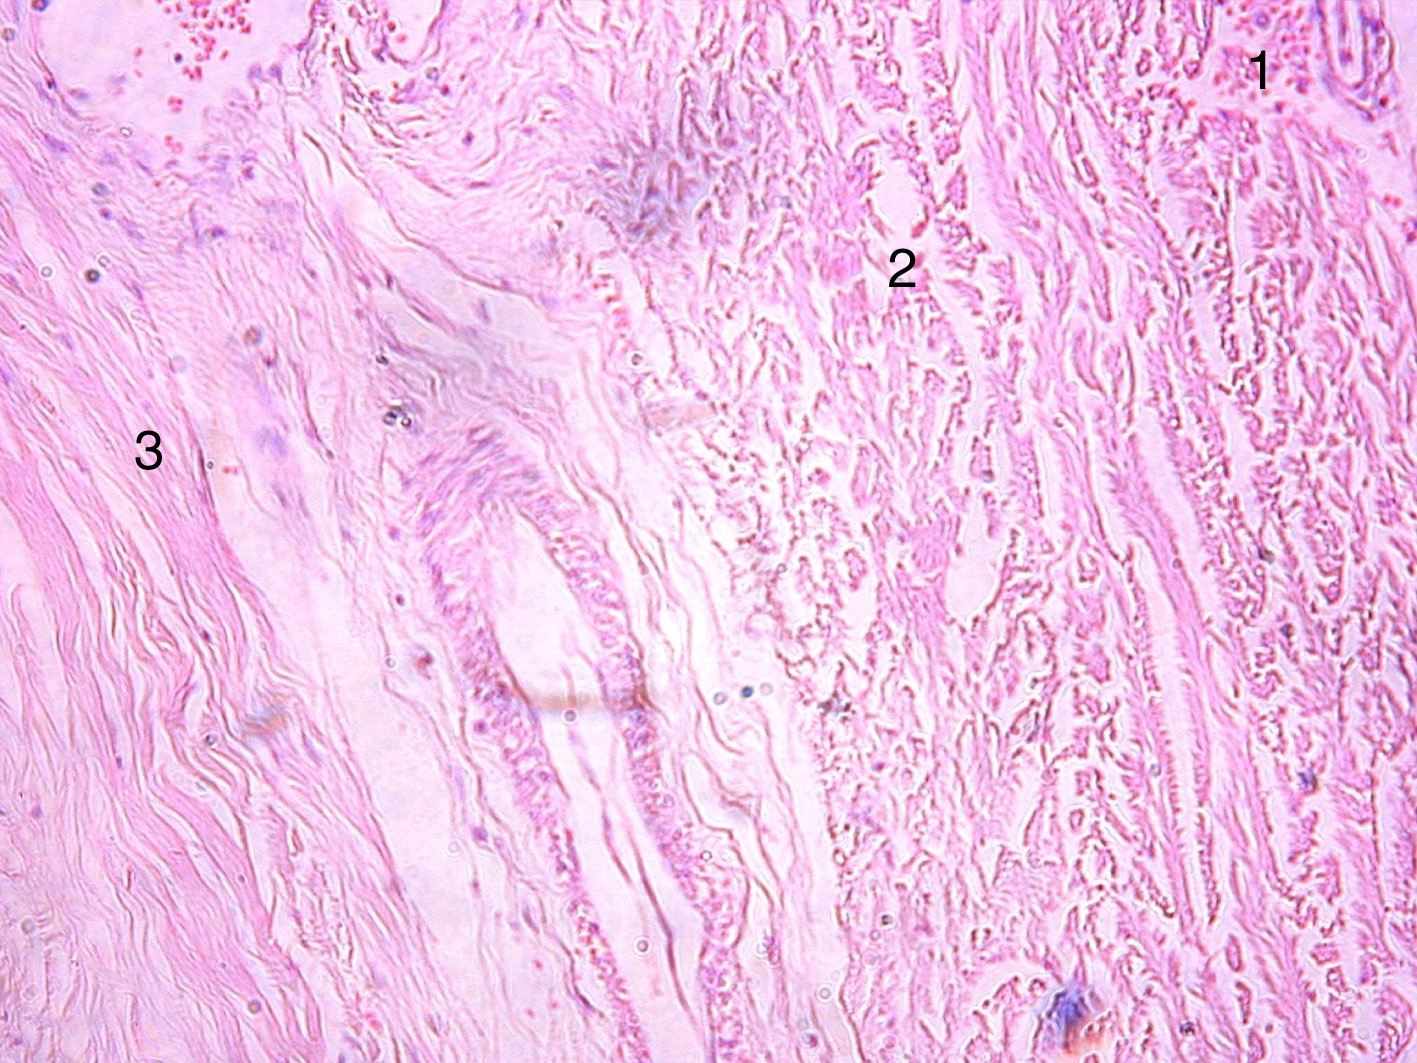

Histological examination showed that the DM is represented by dense, unformed connective tissue containing blood vessels. It has three layers (periosteal, meningeal, and boundary-cellular layers). Some fibroblasts were visualized in the tissue. The uneven thickness and tortuosity of the boundary-cellular layer are noteworthy. Collagen fibers in histological samples of the DM of the early adult group are located relatively compactly and have a clear direction and structure, whereas in the older group, a pronounced disorder of the fibers is visible. Blood vessels are localized mainly in the periosteal layer. The blood vessel wall in the older group is usually thickened (Figs. 2 and 3).

Figure 2. Fragment of the dura mater of a 28-year-old man. Hematoxylin and eosin staining. Magnification 100. 1 – periosteal, 2 – meningeal, 3 – boundary-cellular layer.

Рисунок 2. Фрагмент твердой мозговой оболочки мужчины 28 лет. Окраска гематоксилином и эозином. Увеличение 100. 1 – периостальный, 2 – менингеальный, 3 – погранично-клеточный слои.

Figure 3. Fragment of the dura mater of a 75-year-old man. Hematoxylin and eosin staining. Magnification 100. 1 – periosteal, 2 – meningeal, 3 – boundary-cellular layer.

Рисунок 3. Фрагмент твердой мозговой оболочки мужчины 75 лет. Окраска гематоксилином и эозином. Увеличение 100. 1 – периостальный, 2 – менингеальный, 3 – погранично-клеточный слои.